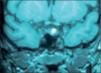

A los 6 meses había ganado peso (89,2kg) y la velocidad de crecimiento era nula. Los estudios del eje adrenal demostraron un cortisol libre urinario elevado (CLU): 131,8μg/24h (60μg/m2/24h), con discreta elevación de los valores de ACTH: 97pg/ml (20–72pg/ml) y cortisol normal (179ng/ml). Los andrógenos adrenales y mineralocorticoides fueron normales. En las pruebas de imagen la ecografía suprarrenal fue normal y en la resonancia magnética (RM) de hipófisis con contraste se observó un microadenoma hipofisario (fig. 2).